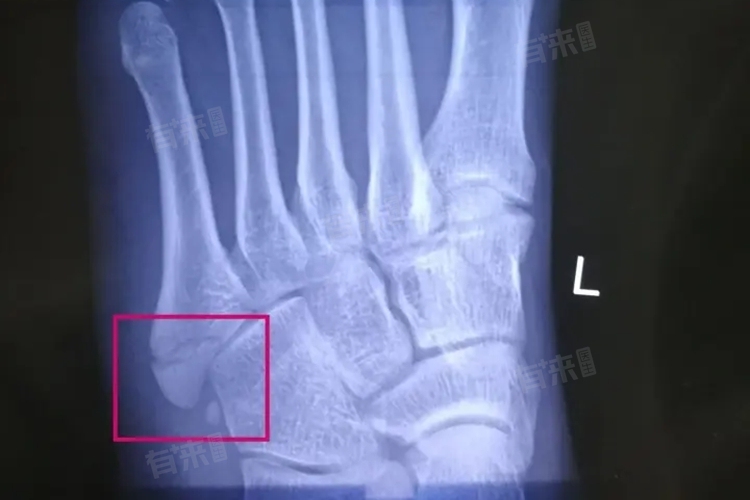

第五指跖骨基底部骨折恢复时间因骨折程度、治疗方法而异,如轻度骨折保守治疗4-8周左右可愈合,严重骨折可能需手术,恢复时间延长至数月,患者应遵医嘱治疗和康复,以促进骨折愈合。

- 严重骨折:如果骨折较为严重,有明显的移位或粉碎性骨折,恢复时间会延长,可能需要8周以上甚至数月的时间,通常需要进行手术治疗,以恢复骨折的对位对线,促进愈合。

- 手术治疗:对于严重骨折或保守治疗效果不佳的患者,可能需要进行手术治疗,可以通过内固定或外固定的方式,将骨折部位固定起来,促进愈合。手术后患者需要遵循医生的建议进行康复训练,恢复关节的活动度和肌肉力量。手术治疗的恢复时间相对较长,可能需要3个月以上。